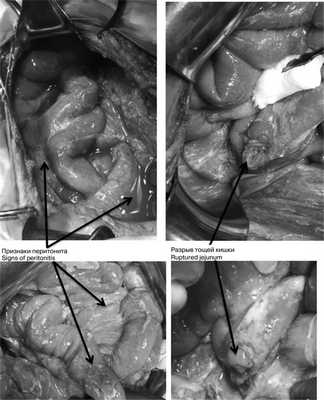

В экстренном порядке выполнена диагностическая видеолапароскопия. При ревизии в брюшной полости около 1000 мл мутного содержимого во всех отделах. Париетальная и висцеральная брюшина тусклая, с наложением фибрина, гиперемирована. При ревизии париетальной брюшины передней брюшной стенки в левом подреберье визуализирован дефект париетальной брюшины и разрыв внутренней косой, поперечной мышц без активного кровотечения размером 4×3 см. Принято решение о конверсии — выполнена широкая срединная лапаротомия. При ревизии тонкой кишки непосредственно за связкой Трейца обнаружен разрыв тощей кишки на 1/3 по противобрыжеечному краю (рис. 2), Рис. 2. Признаки перитонита и разрыва тонкой кишки (интраоперационные фотографии). при осмотре сальниковой сумки выявлено геморрагическое пропитывание парапанкреатической клетчатки. Выполнена назоинтестинальная интубация. Произведена мобилизация участка тощей кишки из-под связки Трейца с иссечением краев разрыва стенки тощей кишки, ушиванием разрыва тощей кишки в поперечном направлении двухрядным швом. Прядь большого сальника фиксирована к линии швов на тощей кишке. Выполнена санация брюшной полости 4 л 0,9% раствора NaCl. Ушит травматический разрыв мышц передней брюшной стенки, двухпросветный дренаж оставлен в ране, выведен через контрапертуру на переднюю брюшную стенку. Двухпросветные дренажи также установлены в подпеченочное пространство справа, в полость малого таза, в левый латеральный канал. С целью дренирования полости сальниковой сумки установлен однопросветный дренаж.